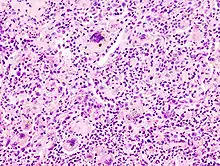

Multinucleated giant cells due to an infection. H&E stain.

A giant cell (also known as a multinucleated giant cell, or multinucleate giant cell) is a mass formed by the union of several distinct cells (usually histiocytes), often forming a granuloma.[1]

Non-osteoclast MGCs can arise in response to an infection, such as tuberculosis, herpes, or HIV, or as part of a foreign body reaction. These MGCs are cells of monocyte or macrophage lineage fused together. Similar to their monocyte precursors, they can phagocytose foreign materials. However, their large size and extensive membrane ruffling make them better equipped to clear up larger particles. They utilize activated CR3s to ingest complement-opsonized targets. Non-osteoclast MGCs are also responsible for the clearance of cell debris, which is necessary for tissue remodeling after injuries.[2]